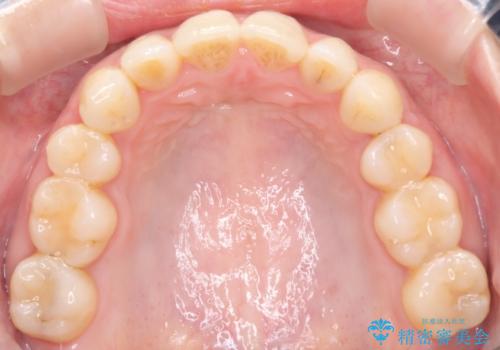

上顎の前歯が前方に傾斜して、下顎の前歯と接触していない状態でした。

上顎の前から4番目の歯を両側抜歯して前歯を後方に移動させる計画としました。